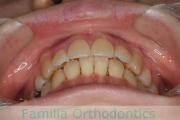

No.23V-061

- 主な症状:

- 叢生

- その他の症状:

- 上下顎前突

- 年齢:

- 23歳

- 性別:

- 女性

- 抜歯部位

- 上:

- 44

- 下:

- 主な使用装置:

- FEA 022

- 治療にかかった費用:

- 88万円

でこぼこを綺麗に並べたいということで来院されました。上下左右から小臼歯を抜歯して、マルチブラケット法を2年半、30回程度通院していただいて行いました。

かなり強い叢生(でこぼこ、凹凸、ガタガタ)のため、保定をしっかりしないと後戻りのリスクが高いケースといえます。

- ≫治療後

-